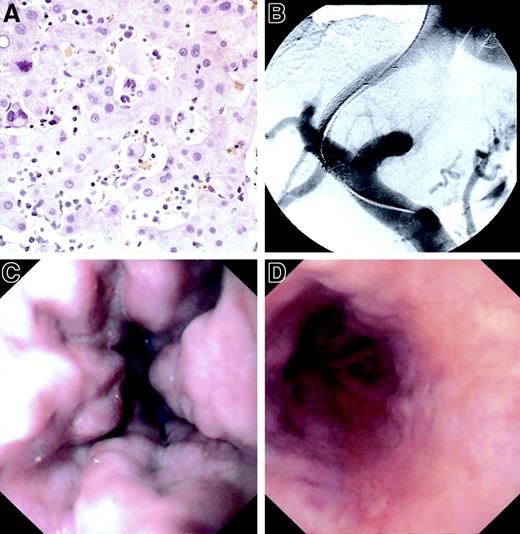

Histologic, radiologic, and endoscopic presentation.

(A) Extramedullary hematopoiesis in dilated sinuses, hematoxylin-eosin staining. Original magnification × 320. (B) TIPS implantation. (C) Oesophagogastroduodenoscopy before TIPS. (D) Oesophagogastroduodenoscopy after TIPS.

A 60-year-old man suffering from IMF for 12 years was referred from the hematology department because of intractable ascites. The patient presented with moderate anemia, normal liver enzymes, and normal liver synthetic function, and showed the abnormalities typical for IMF in his peripheral blood smear (leukoerythroblastic changes, teardrop-shaped cells). On examination, a distinct hepatomegaly, massive splenomegaly (20 × 12 × 30 cm), a dilated splenic vein (30 mm), a patent portal vein with orthograde blood-flow, massive ascites, oesophageal varices (grade III with red-color-signs), and varices of the cardia were found (Figure 1C).

The hepatic venous pressure gradient (HVPG) showed portal hypertension with a pressure gradient of 23 mmHg (upper limit of normal, 6 mmHg). A biopsy specimen of the liver showed noncirrhotic liver parenchyma with normal architecture, discrete portal fibrosis, and massive infiltration of the liver sinusoids with hematopoietic cells (Figure 1A).

Since sinusoidal obstruction by extramedullary blood-forming units is not very different from other forms of intrahepatic portal hypertension and conservative treatment (dietary sodium restriction and high-dose diuretic therapy were unsuccessful), we decided to implant a GoreTex-coated TIPS endoprosthesis (Viatorr, W. L. Gore and Associates, Flagstaff, AZ; diameter: 8 mm, length: 80 mm) (Figure 1B), which shows a much improved patency rate compared with previous uncoated TIPS models (80%-100%, versus 50%, at 1 year).7 The reduction of the HVPG to 14 mmHg was followed by a rapid and lasting relief of ascites and a marked regression of the oesophageal varices (Figure 1D). At 6 months after implantation, the patient was free of ascites but still required moderate doses of diuretics because of the residual portal hypertension (ideal HVPG after TIPS is below 12 mmHg).